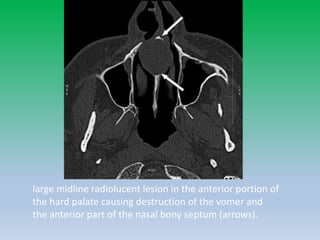

Nasopalatine duct cyst

• A non odontogenic developmental cyst or fissural

cyst arising from epithelial remnants of the

nasopalatine duct.

• Located in anterior hard palate at midline.

• Commonest nonodontogenic cyst.

• On imaging, they appear as round, ovoid, well

defined lucent lesion in the anterior maxilla. The

margin is well defined , smooth and dense rim of

cortical bone is often seen along the periphery.

large midline radiolucent lesion in the anterior portion of

the hard palate causing destruction of the vomer and

the anterior part of the nasal bony septum (arrows).